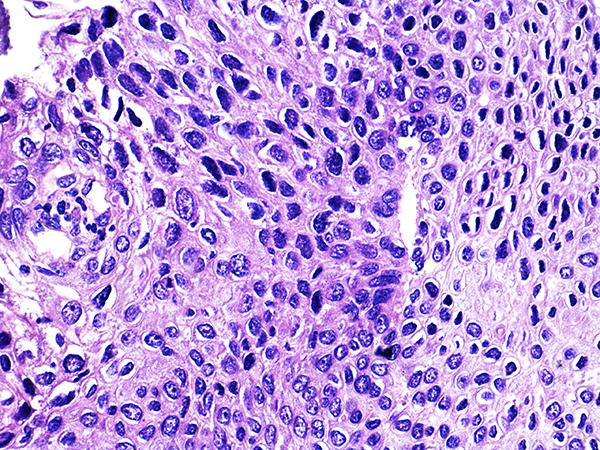

Case 4

Soft Bx CIN 3

40x - High Power